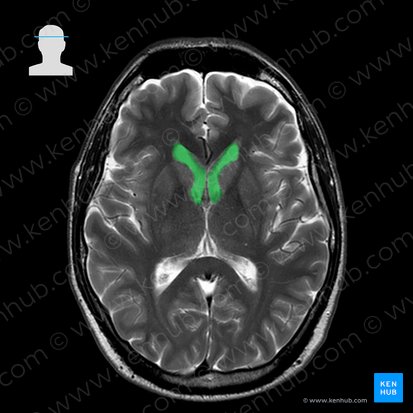

Seitenventrikel

Die Seitenventrikel sind zwei Hohlräume innerhalb des Gehirns, die mit Liquor cerebrospinalis gefüllt sind und sich auf beiden Seiten der Mittellinie befinden. Sie sind die auffälligsten Strukturen auf den meisten MRT-Bildern in der Transversalebene. Wie auch das ganze Ventrikelsystem werden die Seitenventrikel in der T2-Wichtung hyperintens dargestellt, da sie mit Liquor gefüllt sind.

Jeder Seitenventrikel ist eine komplexe dreidimensionale Struktur und besteht aus Vorderhorn, Zentralteil, Hinterhorn und Unterhorn.

Die Vorderhörner sind die größten Bestandteile des Ventrikelsystems. Auf der MRT-Aufnahme erscheinen sie als konkave, nach lateral gewölbte und symmetrische Strukturen. Ihre vorderen Anteile weichen seitlich von der Mittellinie ab und werden vom Knie des Gehirnbalkens (Genu corpori callosi) voneinander getrennt. Die hinteren Anteile der Vorderhörner werden nur durch das Septum pellucidum getrennt, weshalb sie näher beieinander liegen. Die Seitenflächen des Vorderhorns liegen dem Caput und dem Corpus nuclei caudati an.

Der zentrale Abschnitt des Seitenventrikels wölbt sich über den dritten Ventrikel und den Thalamus. Auf der Höhe des Splenium corporis callosi geht der Mittelteil ins Trigonum collaterale über, welches ein flaches dreieckiges Areal bildet. Das Trigonum collaterale befindet sich lateral des Splenium corporis callosi und hat zwei Fortsätze - das Hinterhorn im Okzipitallappen und das Unterhorn im Temporallappen.

Dritter Ventrikel

Der dritte Ventrikel befindet sich zwischen den beiden Hälften des Thalamus und unter dem Hirngewölbe (Fornix cerebri). Auf einem transversalen Schnitt ist er im MRT als schlitzförmige und hyperintense Struktur zu erkennen. Der dritte Ventrikel ist über die Foramina interventricularia (Foramen monroi) mit den Seitenventrikeln und über den Aquaeductus cerebri (Aqueductus mesencephali) mit dem vierten Ventrikel verbunden.

Nachdem du die Ventrikel identifiziert hast, kannst du einschätzen, ob sie pathologische Veränderungen aufweisen. Vergrößerungen oder Verengungen (Stenosen) sind als pathologischer Befund zu deuten. Im Rahmen eines Hydrocephalus staut sich Liquor in den Ventrikeln, sodass diese erweitert werden. Tumore, Abszesse und Hämatome hingegen, können Druck auf die Ventrikel ausüben und sie einengen. Es sollte auf Asymmetrien oder Mittellinienverlagerungen geachtet werden. Ursache hierfür können raumfordernde intrakranielle Prozesse sein, die zu Hirndruck und im schlimmsten Fall zu einer Einklemmung des Gehirns führen. Oftmals werden Raumforderungen durch Tumore oder Hämatome verursacht. In der T2-Wichtung erscheinen sie hyperintens und in der T1-Wichtung hypointens.